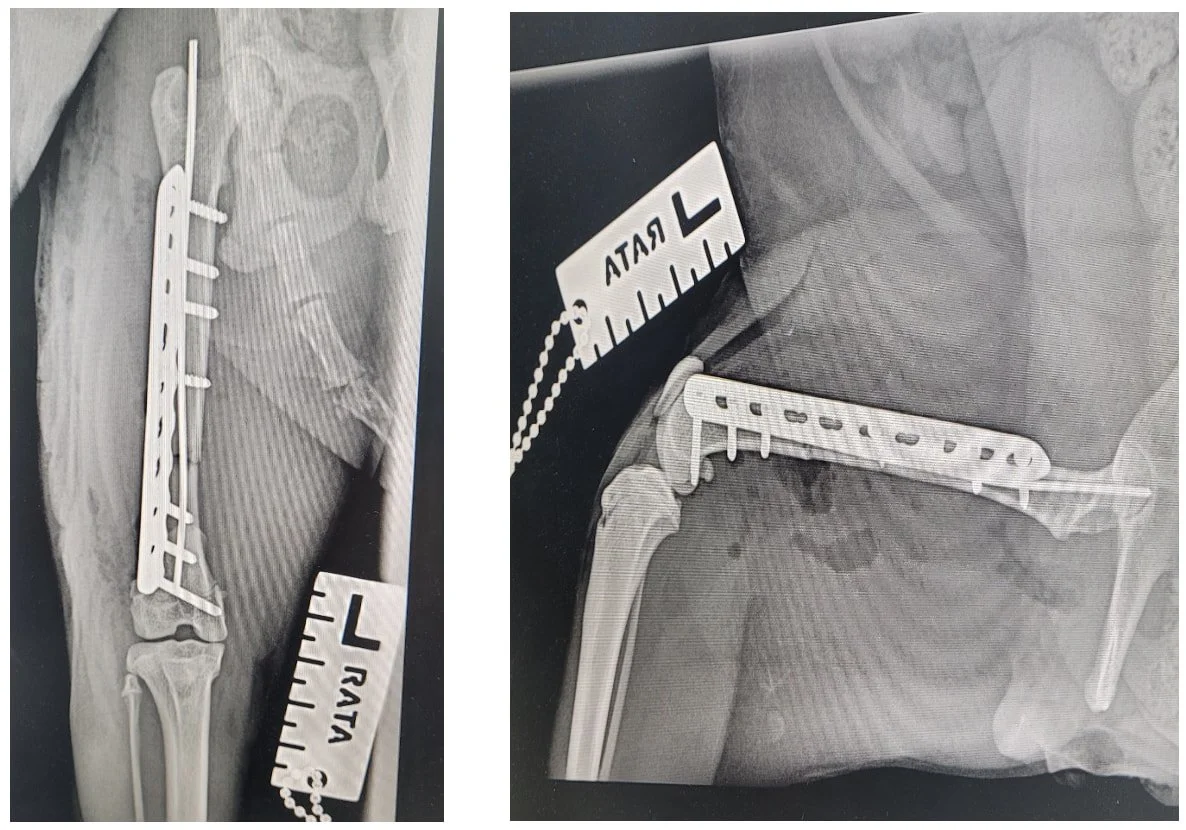

Paddy is a handsome 1 year old cat. He recently had an accident at home he broke his thigh bone. Paddy was in a lot of pain and needed urgent surgery to rectify the problem. A specialist surgeon came at quick request to pin and plate Paddy’s leg so we could save it for him. Paddy is doing really well on recovery, and still remains a happy, chirpy boy. He has been coming in regularly to see us to ensure he is doing well post-surgery.

Before Surgery:

After Surgery: